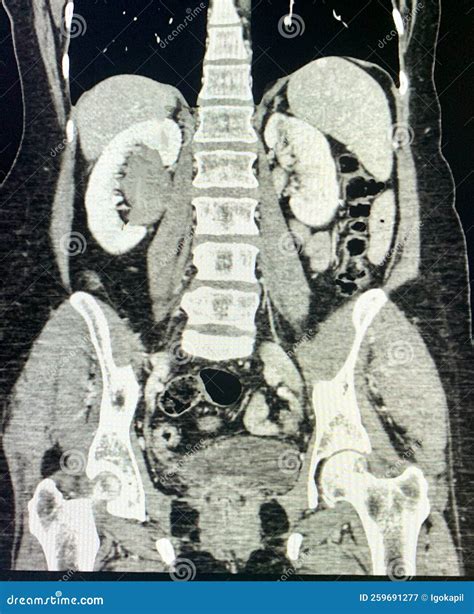

Diagnosing hydronephrosis involves a combination of medical history, physical examination, and diagnostic tests. The goal is to identify the underlying cause of the obstruction and determine the best course of treatment. Common diagnostic tests include:

• CT Scan: A computerized tomography scan that provides detailed images of the internal structures.